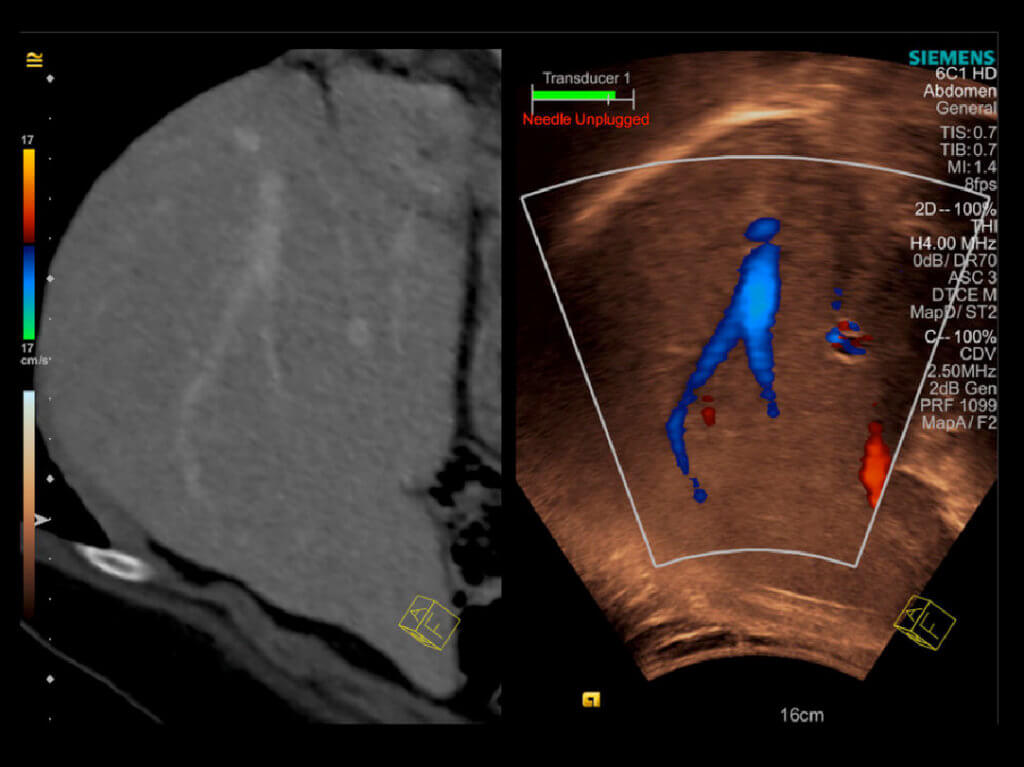

Ein neues sogenanntes Elastographieverfahren, was unserer Praxisklinik seit 1 Jahr zur Verfügung steht, erlaubt uns nicht invasiv, schmerzfrei auf sanfte Art den Ausmaß

der Leberschädigung abzuschätzen, dieses erfolgt durch Messung der Leberelastizität, die bei zunehmender Vernarbung abnimmt. Die Untersuchung erfolgt ambulant mit

einem speziellen Schallkopf, der in Leberhöhe auf der Haut aufgesetzt wird. Im High-Tech-Verfahren wird über Schallwellen die Verformbarkeit der Leber gemessen und

als quantitativer Wert in der Einheit Kilopascal (Kpa) angegeben. Die Elastographie ist auch Ideal um den Verlauf einer chronischen Lebererkrankung zu beurteilen.